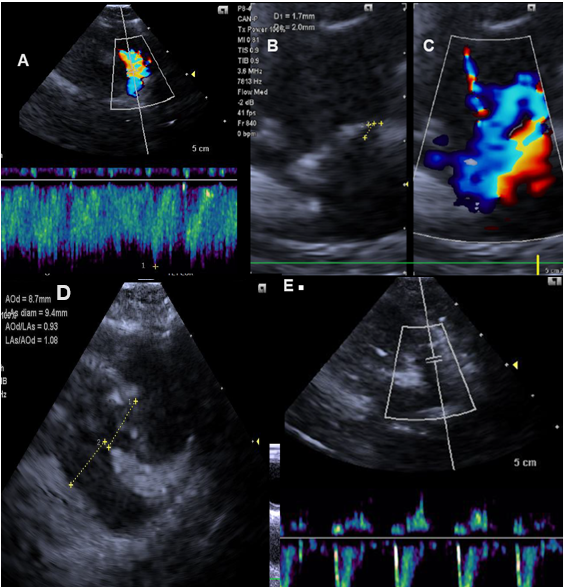

Blood was collected to evaluate the blood count, kidney and liver profile, the results of which were within normal limits for the species. A Doppler echocardiogram was performed with a diagnosis of persistence of right aortic arch with flow from left to right and slight repercussion in the left ventricle (Figure 1A, Figure 1D), no alterations in aortic valve (Figure 1B), but Doppler study and color flow mapping indicate continuous turbulent flow in the pulmonary artery (Figure 1C).

Because this diagnosis, surgery was performed to ligate the duct followed by section of the ligament. Antibiotic therapy was followed with the use of ceftriaxone (25 mg/kg twice a day, 7 days), meloxicam (0.1 mg/kg once a day, 3 days) and tramadol hydrochloride (1 mg/kg, three times a day, 3 days). The post-surgical Doppler echocardiogram showed correction of patent ductus arteriosus, demonstrating the absence of continuous turbulent flow in the pulmonary artery (Figure 1E).

Figure 1 Figure 1 Doppler echocardiogram.

A. Persistent ductus arteriosus with flow from left to right and slight repercussion in the left ventricle.

B. Aortic valve with normal appearance and movement of its valves.

C. Pulmonary valve with normal appearance and movement of the valves. The Doppler study and color flow mapping indicate continuous turbulent flow in the pulmonary artery, characterizing the persistence of patent ductus arteriosus.

D. Presence of a patent ductus arteriosus, measuring 0.17 cm at its opening into the pulmonary artery and 0.2 cm in length from the ductal ampulla.

E. Post-surgical examination for correction of patent ductus arteriosus demonstrating the absence of continuous turbulent flow in the pulmonary artery with reduction in left atrial and ventricular diameters.